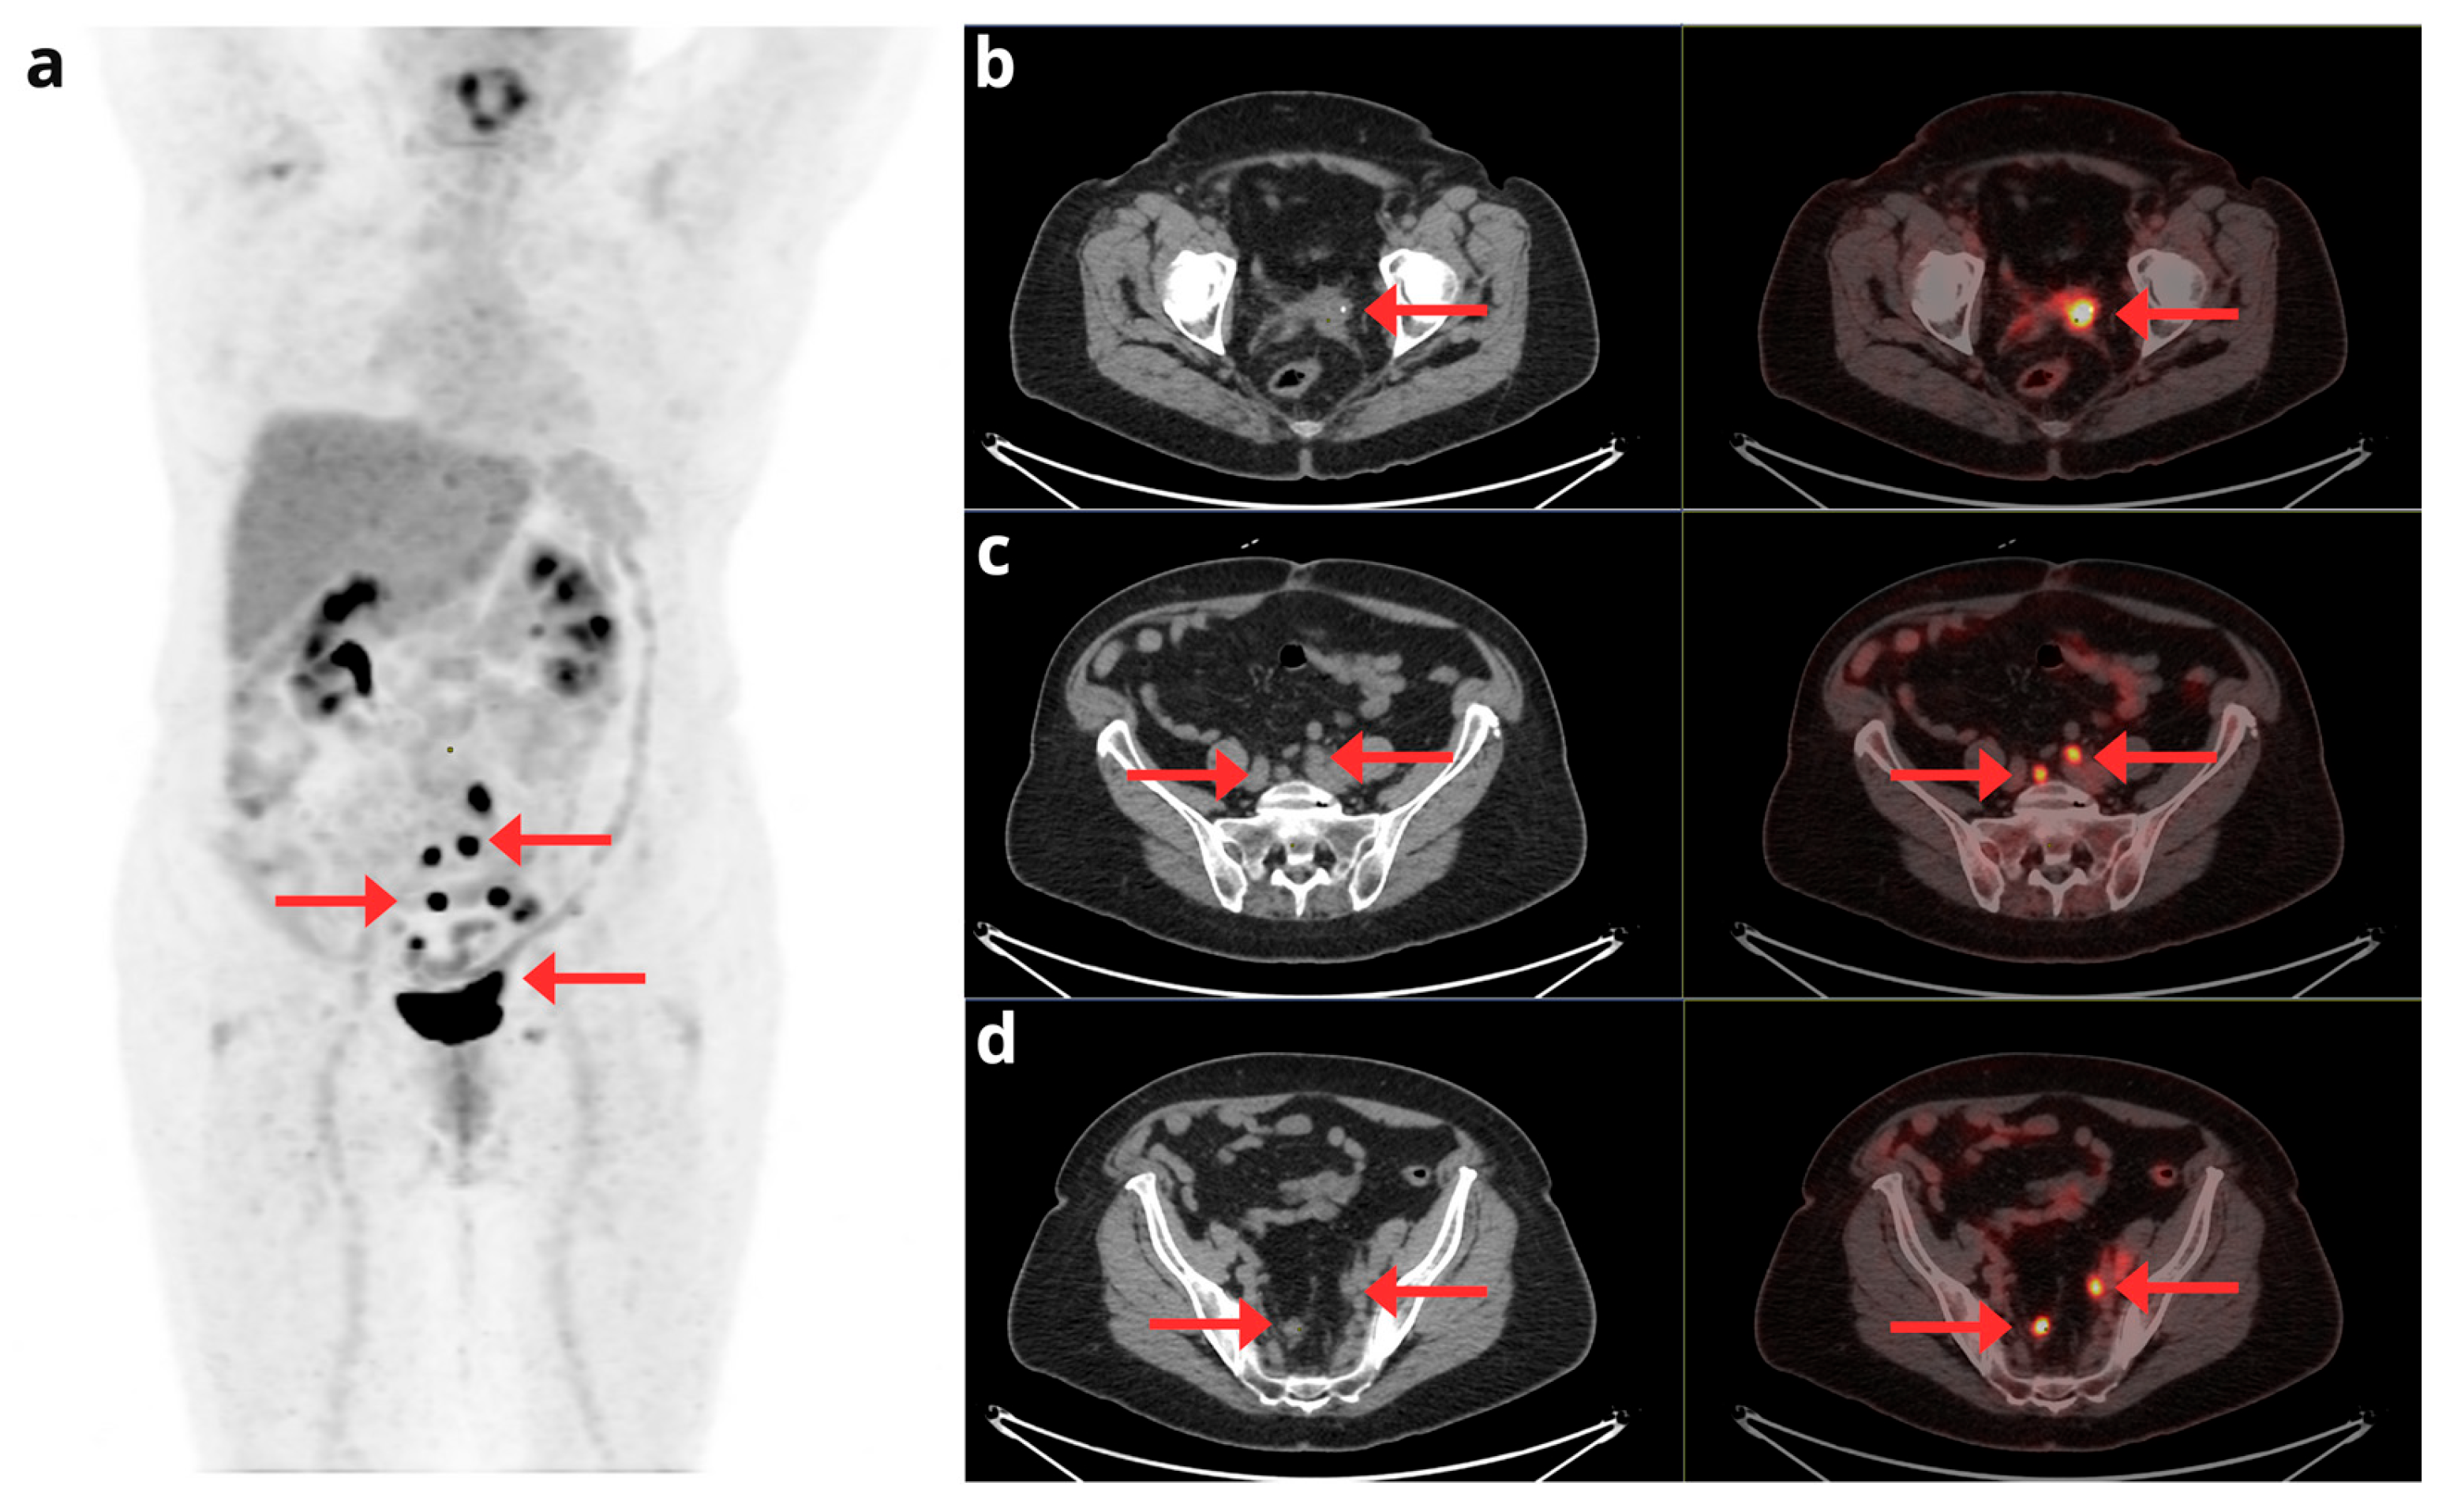

- Kadkhodayan, S.; Shahriari, S.; Treglia, G.; Yousefi, Z.; Sadeghi, R. Accuracy of 18-F-FDG PET Imaging in the Follow up of Endometrial Cancer Patients: Systematic Review and Meta-Analysis of the Literature. Gynecol. Oncol. 2013, 128, 397–404. [CrossRef]

- Chao, A.; Chang, T.-C.; Ng, K.-K.; Hsueh, S.; Huang, H.-J.; Chou, H.-H.; Tsai, C.-S.; Yen, T.-C.; Wu, T.-I.; Lai, C.-H. 18F-FDG PET in the Management of Endometrial Cancer. Eur J Nucl Med Mol Imaging 2006, 33, 36–44. [CrossRef]

- Belhocine, T.; De Barsy, C.; Hustinx, R.; Willems-Foidart, J. Usefulness of 18F-FDG PET in the Post-Therapy Surveillance of Endometrial Carcinoma. Eur J Nucl Med 2002, 29, 1132–1139. [CrossRef]

- Park, J.-Y.; Kim, E.N.; Kim, D.-Y.; KiM, J.-H.; Kim, Y.-M.; Kim, Y.-T.; Nam, J.-H. Clinical Impact of Positron Emission Tomography or Positron Emission Tomography/Computed Tomography in the Posttherapy Surveillance of Endometrial Carcinoma: Evaluation of 88 Patients. International Journal of Gynecological Cancer 2008, 18, 1332–1338. [CrossRef]

- Sawicki, L.M.; Kirchner, J.; Grueneisen, J.; Ruhlmann, V.; Aktas, B.; Schaarschmidt, B.M.; Forsting, M.; Herrmann, K.; Antoch, G.; Umutlu, L. Comparison of 18F–FDG PET/MRI and MRI Alone for Whole-Body Staging and Potential Impact on Therapeutic Management of Women with Suspected Recurrent Pelvic Cancer: A Follow-up Study. Eur J Nucl Med Mol Imaging 2018, 45, 622–629. [CrossRef]

- Crivellaro, C.; Landoni, C.; Elisei, F.; Buda, A.; Bonacina, M.; Grassi, T.; Monaco, L.; Giuliani, D.; Gotuzzo, I.; Magni, S.; et al. Combining Positron Emission Tomography/Computed Tomography, Radiomics, and Sentinel Lymph Node Mapping for Nodal Staging of Endometrial Cancer Patients. Int J Gynecol Cancer 2020, 30, 378–382. [CrossRef]